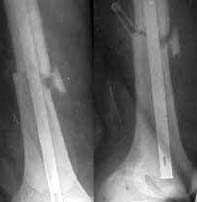

Seeking advice on further management of 26 years old male with femoral nonunion. He sustained femoral shaft fracture in a RTA 3 years ago and was treated with Open K nailing and Thomas Splint 3 years ago. See attached Xray. He was mobilised 3 months later. For about a year he was walking well then he developed pain in his knee. Xray attached show that the K nail had migrated into the Knee joint. K nail was exchanged with dynamic locking nail ( two distal screws - no proximal screw ) by closed technique - no bone grafting done. Patient was symptom free for about 18 months now has come with pain in the knee on weightbearing. Xrays attached show femoral nonunion with loosening of the distal screws (Area of lucency around the screws ). He is short fat male ( 5 feet 4 inches - 90 Kgs ), nonsmoker with no clinical or hematological signs of infection.

AP 2 yrs ago

AP now

Lat now